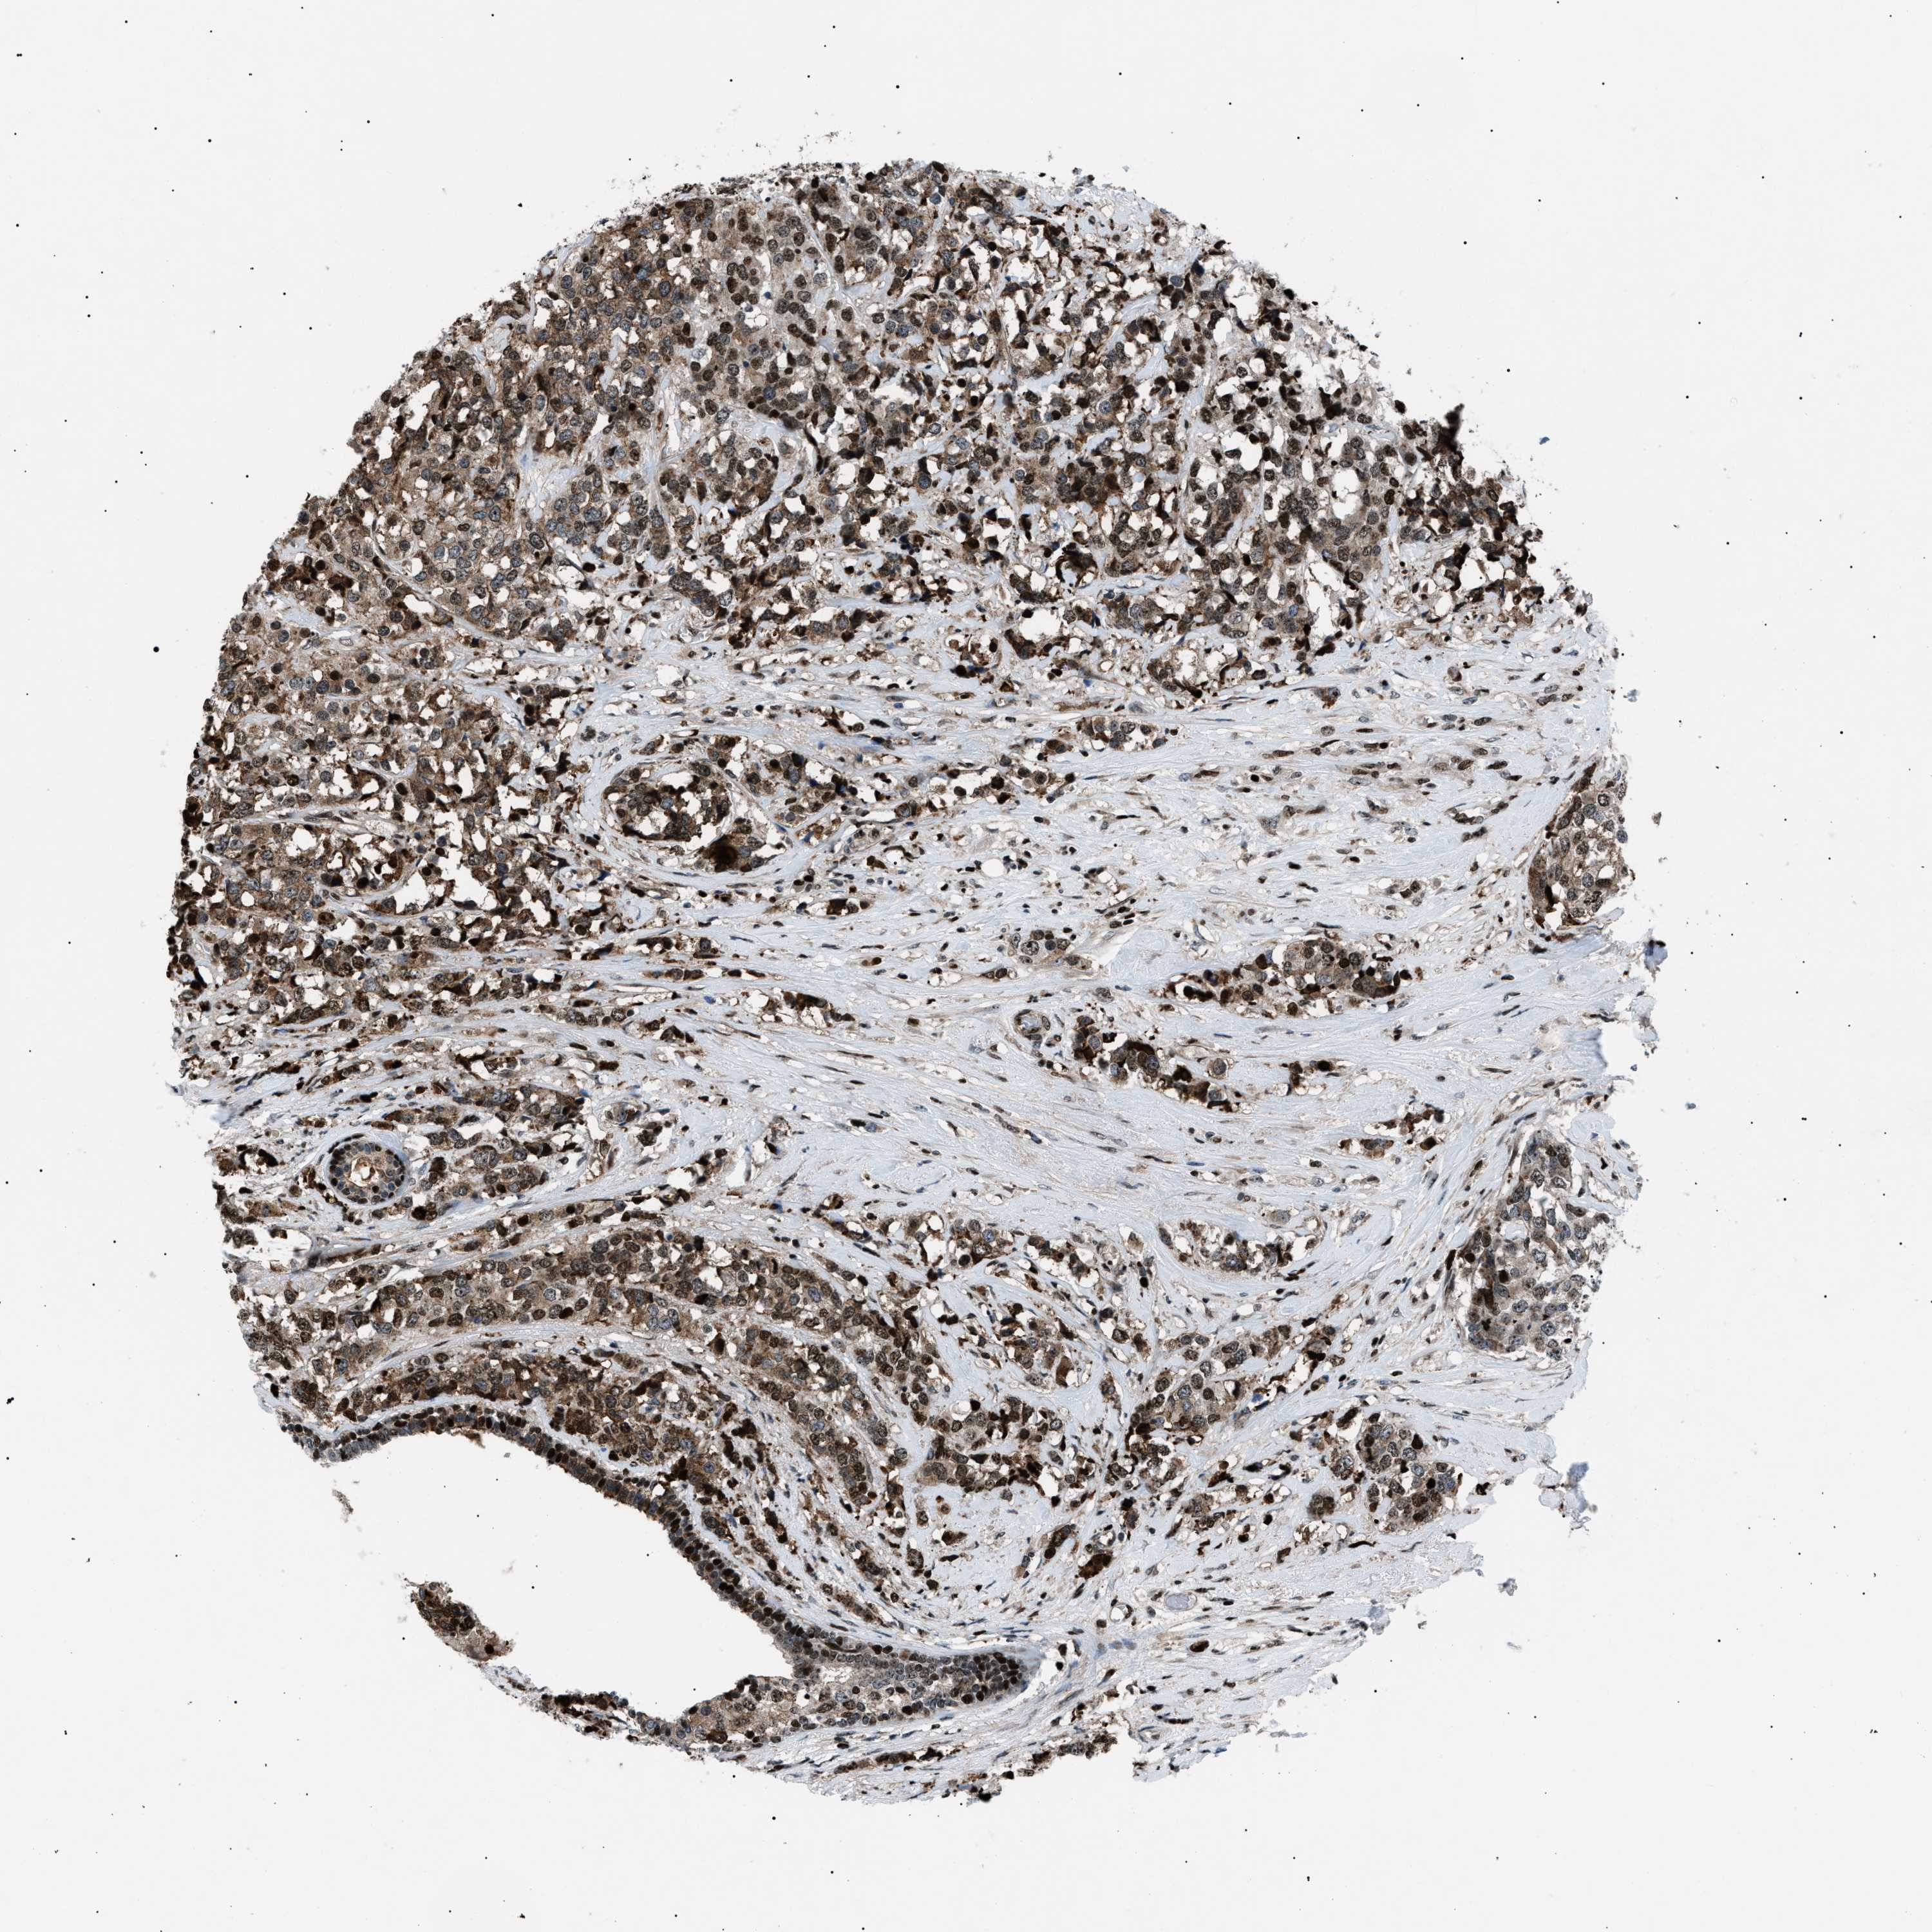

CANCER BREAST CANCER Show tissue menu

BRCA TCGA BRCA VALIDATION PROTEIN EXPRESSION

ANTIBODIES

AND

VALIDATION